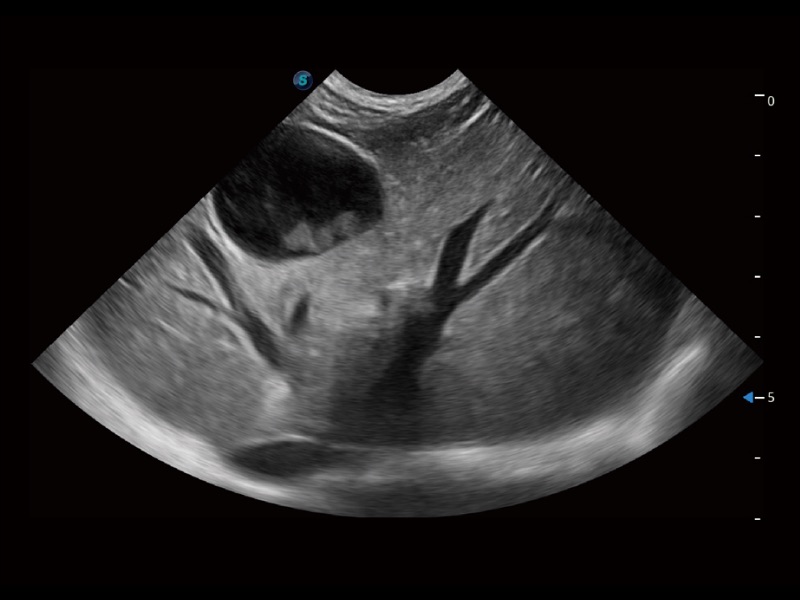

ProPet 70专为动物医生设计,对不同的动物体型和生理结构作出了针对性的优化。通过动物影像专用软件,可满足个性化的应用需求,帮助动物医生获得更精确的诊断数据。